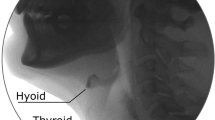

There are various methods for tongue movement measurement during swallowing: videofluoroscopy [3], magnetic resonance imaging [4], and ultrasound [5]. Videofluoroscopy is considered the gold standard for evaluating swallowing; however, there are risks associated with radiation exposure [1]. Ultrasound is simple, repeatable, and its dynamic soft tissue imaging may make it superior to other modalities for swallowing research. The process of swallowing can also be easily seen in real time, or the stream of images can be recorded for later analysis.

Given recent advances that enable the capture and analysis of high-speed B-mode ultrasound [8], we aimed to test this hypothesis and measure certain spatial and dynamic aspects of the swallowing in a consistent manner across participants, using B-mode images captured from a probe located on the submental surface scanning the mid-sagittal plane. Moreover, ultrasound imaging was explored for possible use in the qualitative evaluation of tongue movements associated with different volumes and viscosities.

Producers

Ultrasound data were acquired using an Articulate Instruments EchoB system remotely controlled via USB from a personal computer running Articulate Assistant Advanced (AAA) software version 2.16 [8]. The echo return data were recorded at the rate of 54 frames per second (fps) with 127 beam-formed echo pulses evenly spread over a 104° field of view (FOV) providing a resolution of approximately 0.8°, so when the tongue’s surface is 5 cm from the probe, the distance between the scanlines is under 1 mm. The depth setting was 90 mm, and the resolution along each scanline is well below 1 mm. Standard graphical interpolation was performed on the raw data to convert it to an image for analysis in AAA, similar to the image processing that is normally carried out within a dedicated ultrasound scanner. The low-frequency convex transducer frequency operated at 4 MHz. The participant was fitted with a headset to stabilize the ultrasound probe (Fig. 1).

Ultrasound tongue imaging (UTI) captures spatial aspects of swallowing as they change in time. Dodds et al. [3] reported that swallowing is divided into four phases: the preparatory phase, oral phase, pharyngeal phase, and esophageal phase. During the preparatory phase, the bolus is sized, shaped, and positioned on the tongue ready for swallowing, and during the oral phase, the bolus is propelled from the oral cavity into the pharynx. Thus, ultrasound is well suited to analyze the preparatory and oral phases because the floor of the mouth is an accessible and relatively small area, and ultrasound is able to provide valuable information about the changing location and shape of the tongue’s surface. This could be applied to other types of data, such as magnetic resonance imaging (MRI), computed tomography (CT), and other techniques. Moreover, given the frame rate of the UTI system described, and the wide field of view, the recording of almost complete tongue movements was achieved. The linear measurement of the depression depth allows a quantitative description of the tongue curve spline on B-mode imaging [10].

The present study used only a UTI system for simple tongue shape analysis. UTI is good at showing the tongue’s surface and bolus, and less than good at revealing contact between the tongue and hard palate. This makes it difficult to define a temporal reference point comparable to other approaches in the literature. However, electromyography (EMG), electropalatography (EPG), or MRI may provide better means of detecting tongue’s position in the oral cavity, including the time point at which the tongue makes contact with the hard plate.